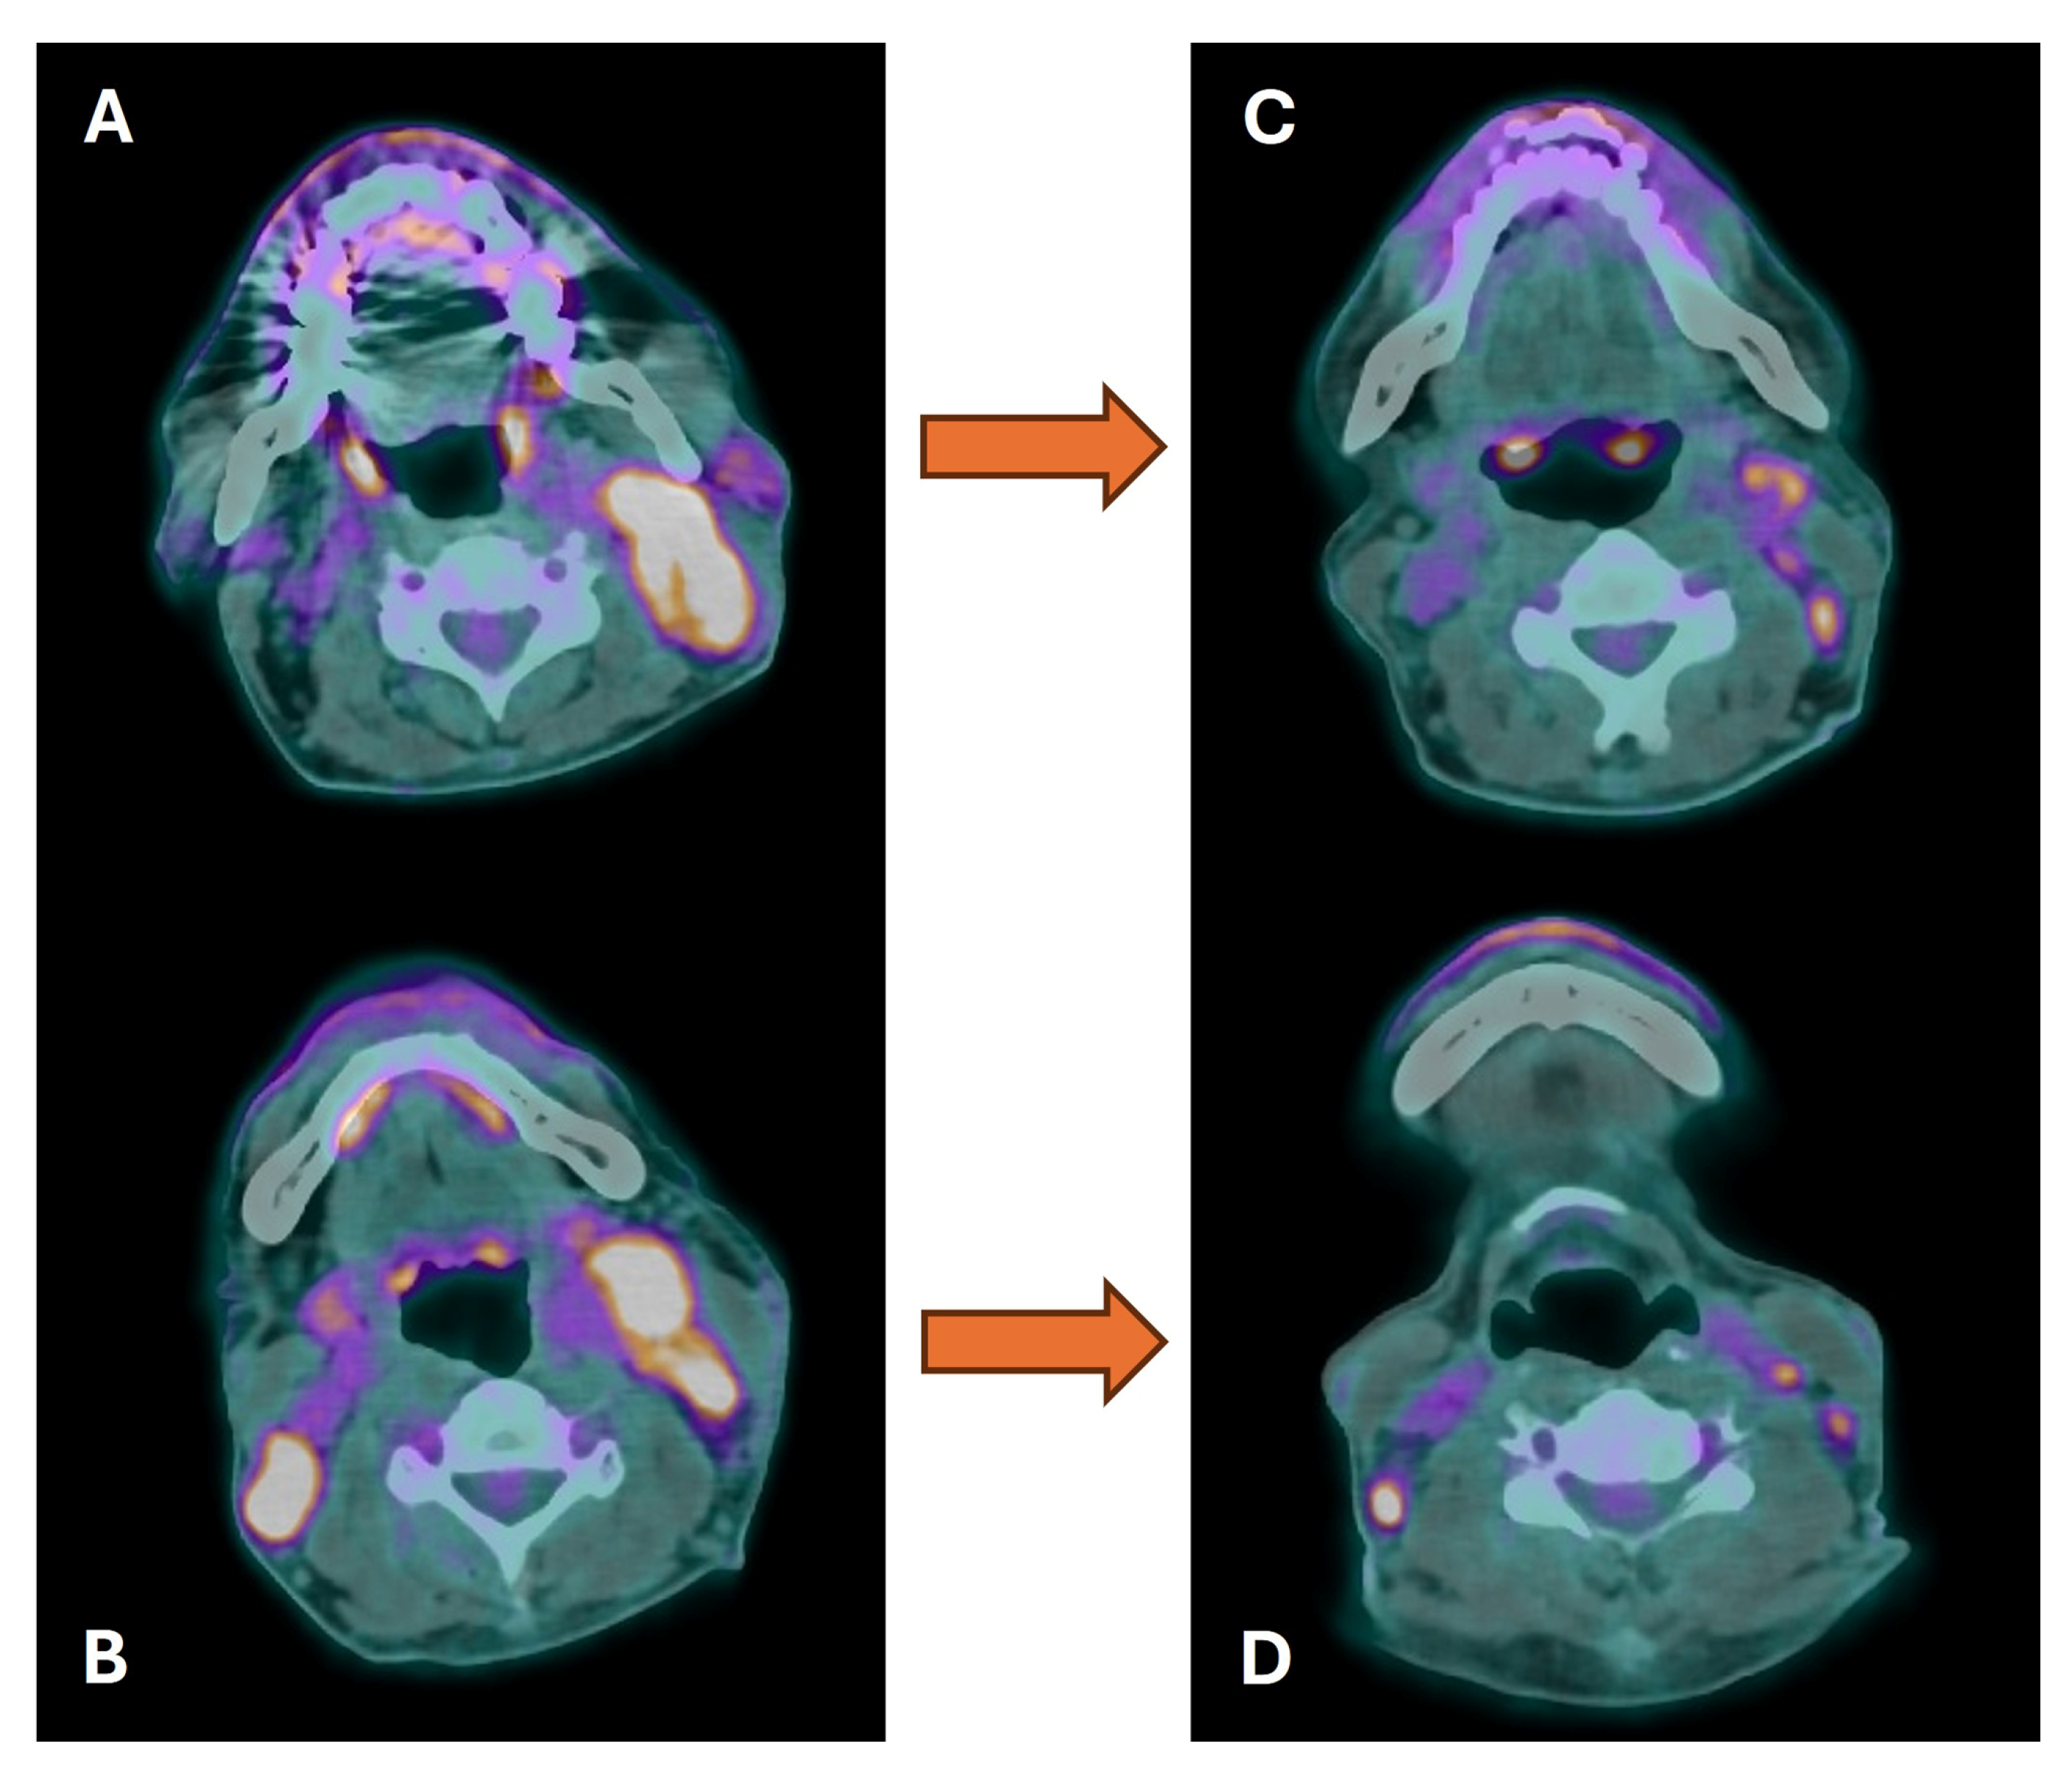

4. Radiotherapy Planning

- Thureau, S.; Briens, A.; Decazes, P.; Castelli, J.; Barateau, A.; Garcia, R.; Thariat, J.; de Crevoisier, R. PET and MRI guided adaptive radiotherapy: Rational, feasibility and benefit. Cancer Radiother. 2020, 24, 635–644. [Google Scholar] [CrossRef]

- van den Bosch, S.; Vogel, W.V.; Raaijmakers, C.P.; Dijkema, T.; Terhaard, C.H.J.; Al-Mamgani, A.; Kaanders, J.H.A.M. Implications of improved diagnostic imaging of small nodal metastases in head and neck cancer: Radiotherapy target volume transformation and dose de-escalation. Radiother. Oncol. 2018, 128, 472–478. [Google Scholar] [CrossRef]

- van den Bosch, S.; Dijkema, T.; Kunze-Busch, M.C.; Terhaard, C.H.; Raaijmakers, C.P.; Doornaert, P.A.; Hoebers, F.J.; Vergeer, M.R.; Kreike, B.; Wijers, O.B.; et al. Uniform FDG-PET guided GRAdient Dose prEscription to reduce late Radiation Toxicity (UPGRADE-RT): Study protocol for a randomized clinical trial with dose reduction to the elective neck in head and neck squamous cell carcinoma. BMC Cancer 2017, 17, 208. [Google Scholar] [CrossRef]

- Manca, G.; Vanzi, E.; Rubello, D.; Giammarile, F.; Grassetto, G.; Wong, K.K.; Perkins, A.C.; Colletti, P.M.; Volterrani, D. 18F-FDG PET/CT quantification in head and neck squamous cell cancer: Principles, technical issues and clinical applications. Eur. J. Nucl. Med. Mol. Imaging 2016, 43, 1360–1375. [Google Scholar] [CrossRef]

- Daisne, J.F.; Duprez, T.; Weynand, B.; Lonneux, M.; Hamoir, M.; Reychler, H.; Grégoire, V. Tumour volume in pharyngolaryngeal squamous cell carcinoma: Comparison at CT, MR imaging, and FDG PET and validation with surgical specimen. Radiology 2004, 233, 93–100. [Google Scholar] [CrossRef]

- Chatterjee, S.; Frew, J.; Mott, J.; McCallum, H.; Stevenson, P.; Maxwell, R.; Wilsdon, J.; Kelly, C. Variation in Radiotherapy Target Volume Definition, Dose to Organs at Risk and Clinical Target Volumes using Anatomic (Computed Tomography) versus Combined Anatomic and Molecular Imaging (Positron Emission Tomography/Computed Tomography): Intensity-modulated Radiotherapy Delivered using a Tomotherapy Hi Art Machine: Final Results of the VortigERN Study. Clin. Oncol. 2012, 24, e173–e179. [Google Scholar]

- Geets, X.; Tomsej, M.; Lee, J.A.; Duprez, T.; Coche, E.; Cosnard, G.; Lonneux, M.; Grégoire, V. Adaptive biological image-guided IMRT with anatomic and functional imaging in pharyngo-laryngeal tumors: Impact on target volume delineation and dose distribution using helical tomotherapy. Radiother. Oncol. 2007, 85, 105–115. [Google Scholar] [CrossRef]

- Guido, A.; Fuccio, L.; Rombi, B.; Castellucci, P.; Cecconi, A.; Bunkheila, F.; Fuccio, C.; Spezi, E.; Angelini, A.L.; Barbieri, E. Combined 18F-FDG-PET/CT Imaging in Radiotherapy Target Delineation for Head-and-Neck Cancer. Int. J. Radiat. Oncol. 2009, 73, 759–763. [Google Scholar] [CrossRef] [PubMed]

- Lapa, C.; Nestle, U.; Albert, N.L.; Baues, C.; Beer, A.; Buck, A.; Budach, V.; Bütof, R.; Combs, S.E.; Derlin, T.; et al. Arbeitsgemeinschaft Nuklearmedizin und Strahlentherapie der DEGRO und DGN. Value of PET imaging for radiation therapy. Strahlenther. Onkol. 2021, 197, 1–23, Erratum in: Strahlenther. Onkol. 2022, 198, 80–82. [Google Scholar] [CrossRef] [PubMed]

| PET/CT and Radiotherapy Planning | Clinical Examples |

|---|---|

| Patient selection and intended management | Treatment (local disease) versus non-treatment (distant metastases) |

| Goal of treatment | From curative to palliative and vice versa |

| Selection and delineation of GTV | - Detection of occult primary tumor (see text) - Tumor extension not defined on CT or MRI (see Figure 3) |

| Dose painting based on biological tumor features | Dose escalation to 18F-FDG avid or hypoxic sub-volumes |

| Adaptive radiotherapy | Escalation or de-escalation during treatment |